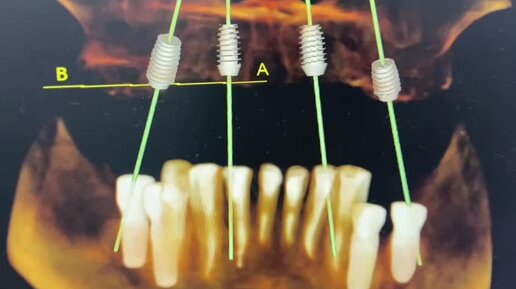

Оборудование стоматологов, операция в кресле стоматолога.

О здоровье простыми словами. Альфа-стоматология